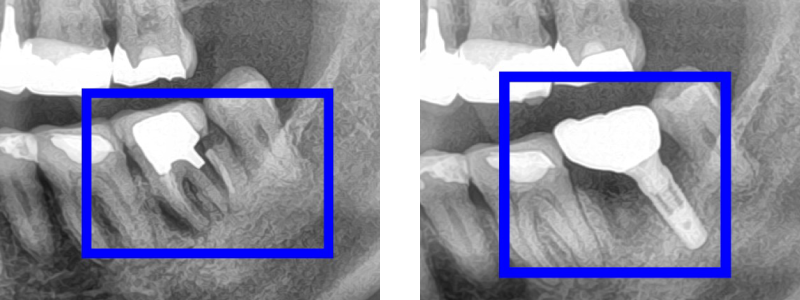

インプラント症例

治療内容 60代男性 割れていた歯を抜歯しインプラント埋入

期間 約2ヵ月

費用 385,000円

(インプラント275,000円+骨再生100,000円)

注意点/副作用 外科処置が必要・全身状態によりできない場合がある。